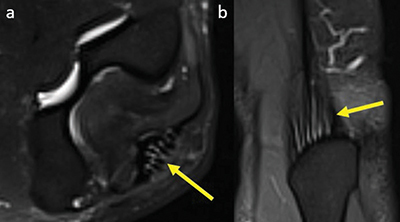

Materials and methods: Two hundred and five magnetic resonance imaging (MRI) exams of the elbow with coronal and axial fat-saturated fluid-sensitive sequences between January 1, 2018 and July 31, 2022 were retrospectively identified in our center.Two radiology residents reviewed the exams independently. The elbow tendons were given a score from 0 to 4. Score 0: no signal abnormality; score 1: increased T2-weighted signal around the tendon; score 2: increased T2-weighted signal compared to muscle within the tendon; score 3: partial tear; and score 4: complete tear.

Results: The common flexor tendon showed signal alterations in 8% of patients; nine patients had an increased signal around the tendon, and eight patients had an increased signal within the tendon. Three patients (1.5%) had an altered signal intensity in the biceps tendon. All triceps tendons showed a linear hyperintense signal, suggesting that it is physiological. There were no partial or complete tears. No signal abnormalities were noted in the brachialis tendon among all patients.

Abstract Image